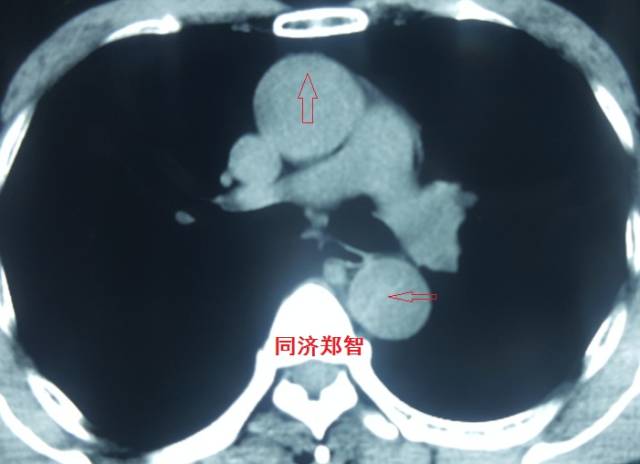

病例十一

平扫CT发现主动脉血管内孤立的钙化点(红色箭头所示),CTA证实为降主动脉溃疡合并壁间血肿。